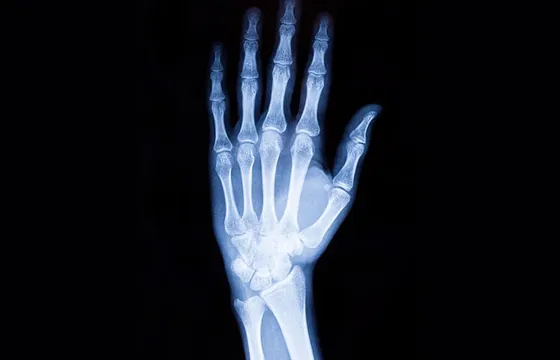

Jak wygląda diagnostyka? RTG, USG, a może rezonans magnetyczny?

Proces diagnostyczny po skręceniu nadgarstka zawsze rozpoczyna się od szczegółowego wywiadu z pacjentem oraz badania fizykalnego. Lekarz ocenia ból, obrzęk, zakres ruchomości i stabilność stawu. Następnie, aby potwierdzić diagnozę i wykluczyć inne urazy, zleca badania obrazowe:

- RTG (rentgen): To podstawowe badanie, które pozwala wykluczyć złamania kości nadgarstka. Jest szybkie i łatwo dostępne.

- USG (ultrasonografia): Jeśli RTG nie wykaże złamania, a objawy nadal wskazują na uraz więzadeł, USG może być pomocne w ocenie tkanek miękkich więzadeł, ścięgien i torebki stawowej.

- Rezonans magnetyczny (MRI): W przypadku wątpliwości diagnostycznych, podejrzenia poważnego uszkodzenia więzadeł (np. całkowitego zerwania) lub innych struktur wewnętrznych, rezonans magnetyczny jest najdokładniejszym badaniem. Pozwala on na precyzyjną ocenę stanu wszystkich tkanek miękkich nadgarstka.